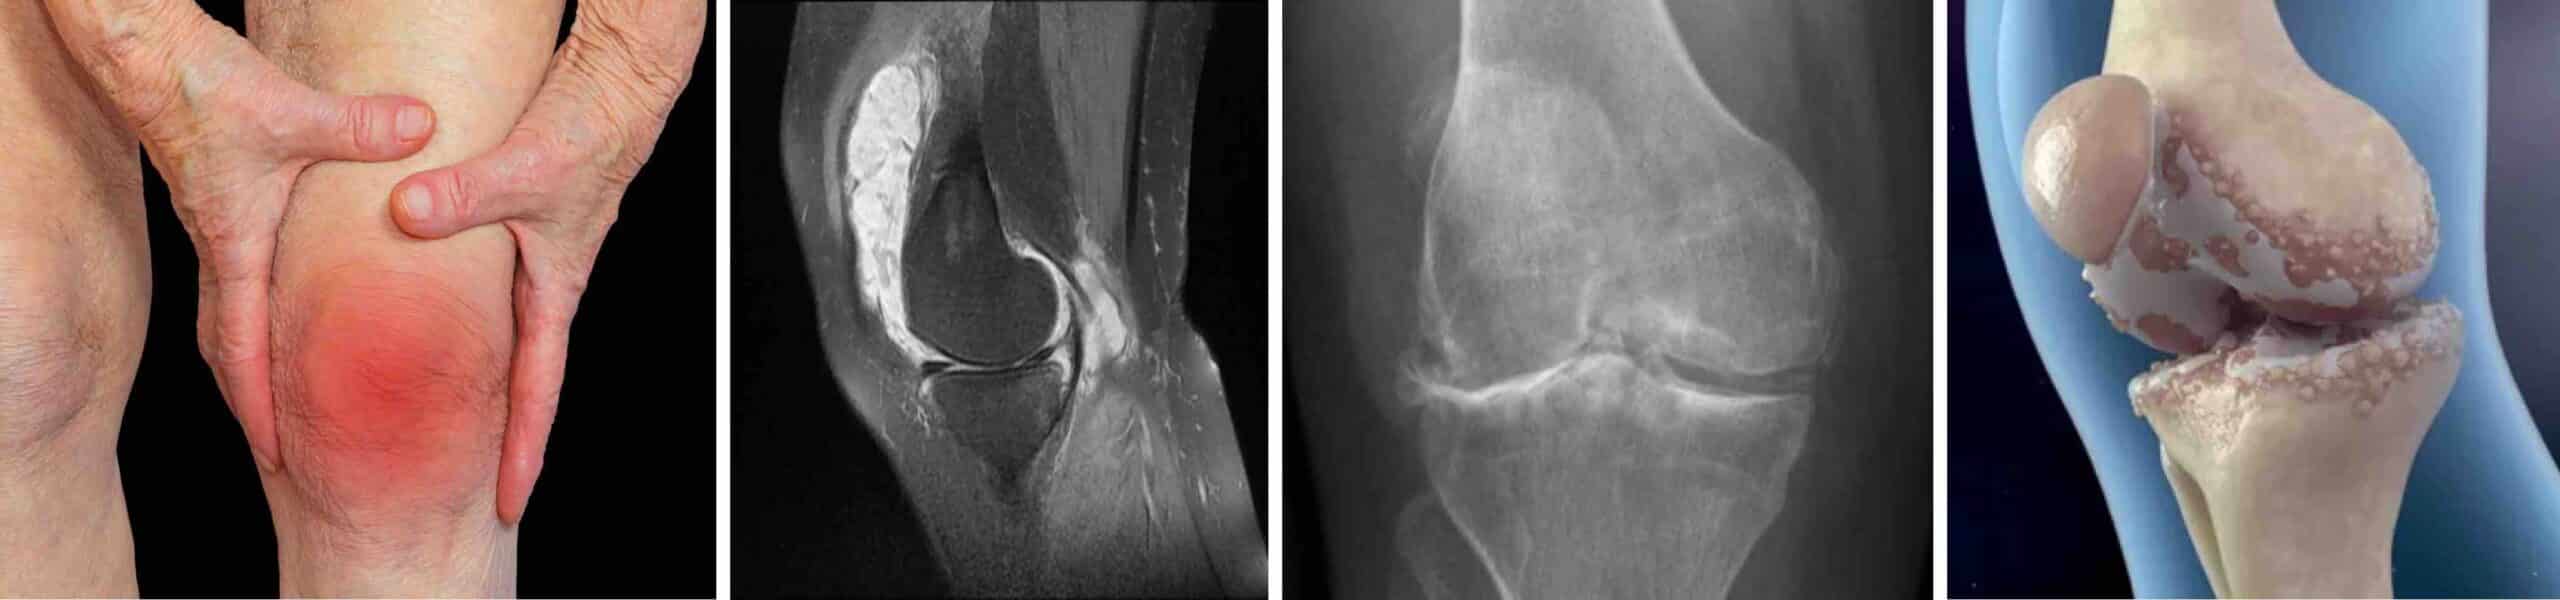

O joelho é a maior e mais complexa articulação do nosso corpo. Ele pode ser acometido por lesões e diversas doenças. Muitas doenças do joelho podem ser tratadas de forma conservadora, sem cirurgia, com a aplicação de medicamentos diretamente na articulação. A infiltração articular no joelho é o procedimento médico para aplicar medicamentos, com o uso de uma seringa com agulha, diretamente no espaço articular. Existem muitas vantagens em se aplicar remédios diretamente dentro do joelho. Ter o efeito mais intenso, mais rápido e mais duradouro são as principais vantagens. Muitas doenças do joelho exigem tratamento com remédios anti-inflamatórios, que podem ser aplicados diretamente no joelho através de uma infiltração articular. No grupo dos medicamentos anti-inflamatórios estão os medicamentos conhecidos como corticóides. E dentro do grupo dos corticóides existe um chamado triancinolona, que tem características próprias ideais para ser aplicado na articulação do joelho.

A infiltração de Triancil® no joelho é ideal para aliviar dores e diminuir processos inflamatórios articulares causados por doenças inflamatórias, degenerativas e autoimunes. O procedimento é indicado para o tratamento de diversas afecções. As principais indicações clínicas são: artrose, artrites, sinovite, condromalácia, condropatias, hoffite, gota, lesões ligamentares e inflamação persistente pós-traumática ou pós-artroscopia. As infiltrações de Triancil® no joelho também podem ser feitas nos tecidos ao redor do joelho, fora do espaço articular, para o tratamento principalmente de bursites, tendinites, tenossinovites e tendinoses.